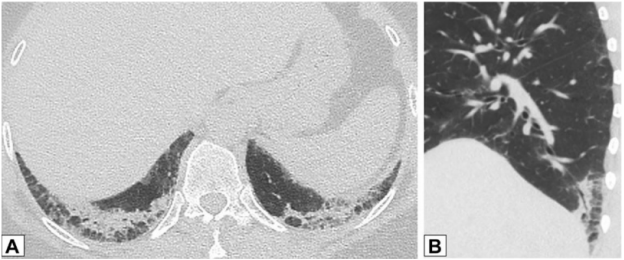

图源:Chest, 2022, 162(1):156-178.其他表现还包括小叶周围增厚和具有反晕外观特征的病变(环礁征)。图15所示为一名慢性持续性咳嗽和劳力性呼吸困难1年、体重减轻的32岁男性患者的CT图像,双侧中心磨玻璃样病灶完全被周围致密实变所包围,即反晕征或环礁征(A、B中红色箭头)。也存在不完全晕征(A、B中白色箭头)和小叶周围增厚(B中黄色箭头)。肺活检结果证实为OP。图源:Chest, 2022, 162(1):156-178.当以线性或网状为主的OP进一步发展,在周围实变或磨玻璃影后,基底和胸膜下网状形成,提示间质纤维化的发展。图16为一名73岁男性患者在呼吸困难发作4 d后获得的CT图像,分别在隆突水平(A,C)和以及肺基底水平(B,D)获得胸部CT图像。2019年的增强图像(A和B)显示双侧广泛的磨玻璃影;2021年的图像(C和D)显示磨玻璃影程度改善,但出现网状和牵拉性支气管扩张或细支气管扩张,这一模式与纤维化相符。右肺上、中、下叶的楔形活检结果显示OP。图源:Chest, 2022, 162(1):156-178.OP可导致广泛的双基底牵引性支气管扩张,其结果与非特异性间质性肺炎(NSIP)相似,并经常重叠。图17为51岁女性皮肌炎患者CT平扫图像,下肺基底图像显示双肺下叶实变,双侧胸膜下和磨玻璃影。矢状位图像上支气管明显扩张(B)。这些表现与OP和NSIP重叠一致。图源:Chest, 2022, 162(1):156-178.一名病态肥胖且进行性呼吸困难的67岁男性患者进行了CT扫描(图18)。肺基底部CT显示周围支气管壁增厚,伴有边界不清的磨玻璃密度和小叶周围增厚,特别是在左基底部(箭头),这些表现提示NSIP。外科肺活检结果与OP相符。

图14 实质条带